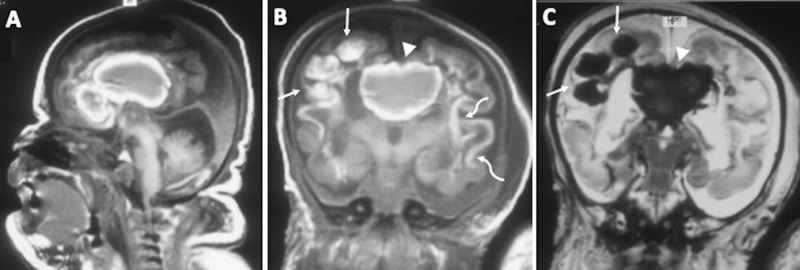

Hemorrhagic Destruction of the Brain, Subependymal Calcification, and Congenital Cataracts (HDBSCC) is a rare syndrome caused by biallelic mutations in the JAM3 gene with significant intrafamilial variability in clinical presentation and brain imaging phenotypes. The clinical presentation of HDBSCC includes severe recurrent hemorrhages involving the brain parenchyma and the ventricles beginning in utero and continuing in infancy together with dense central cataracts present at birth. This comprehensive review documents reported cases on this unique condition and describes its genetic, neuroradiologic and ophthalmic features. It should be included in the differential diagnosis of children with congenital cataracts and neurodevelopmental abnormalities. Unique clinical, imaging findings and genetic testing can help the diagnosis.

Abstract Image